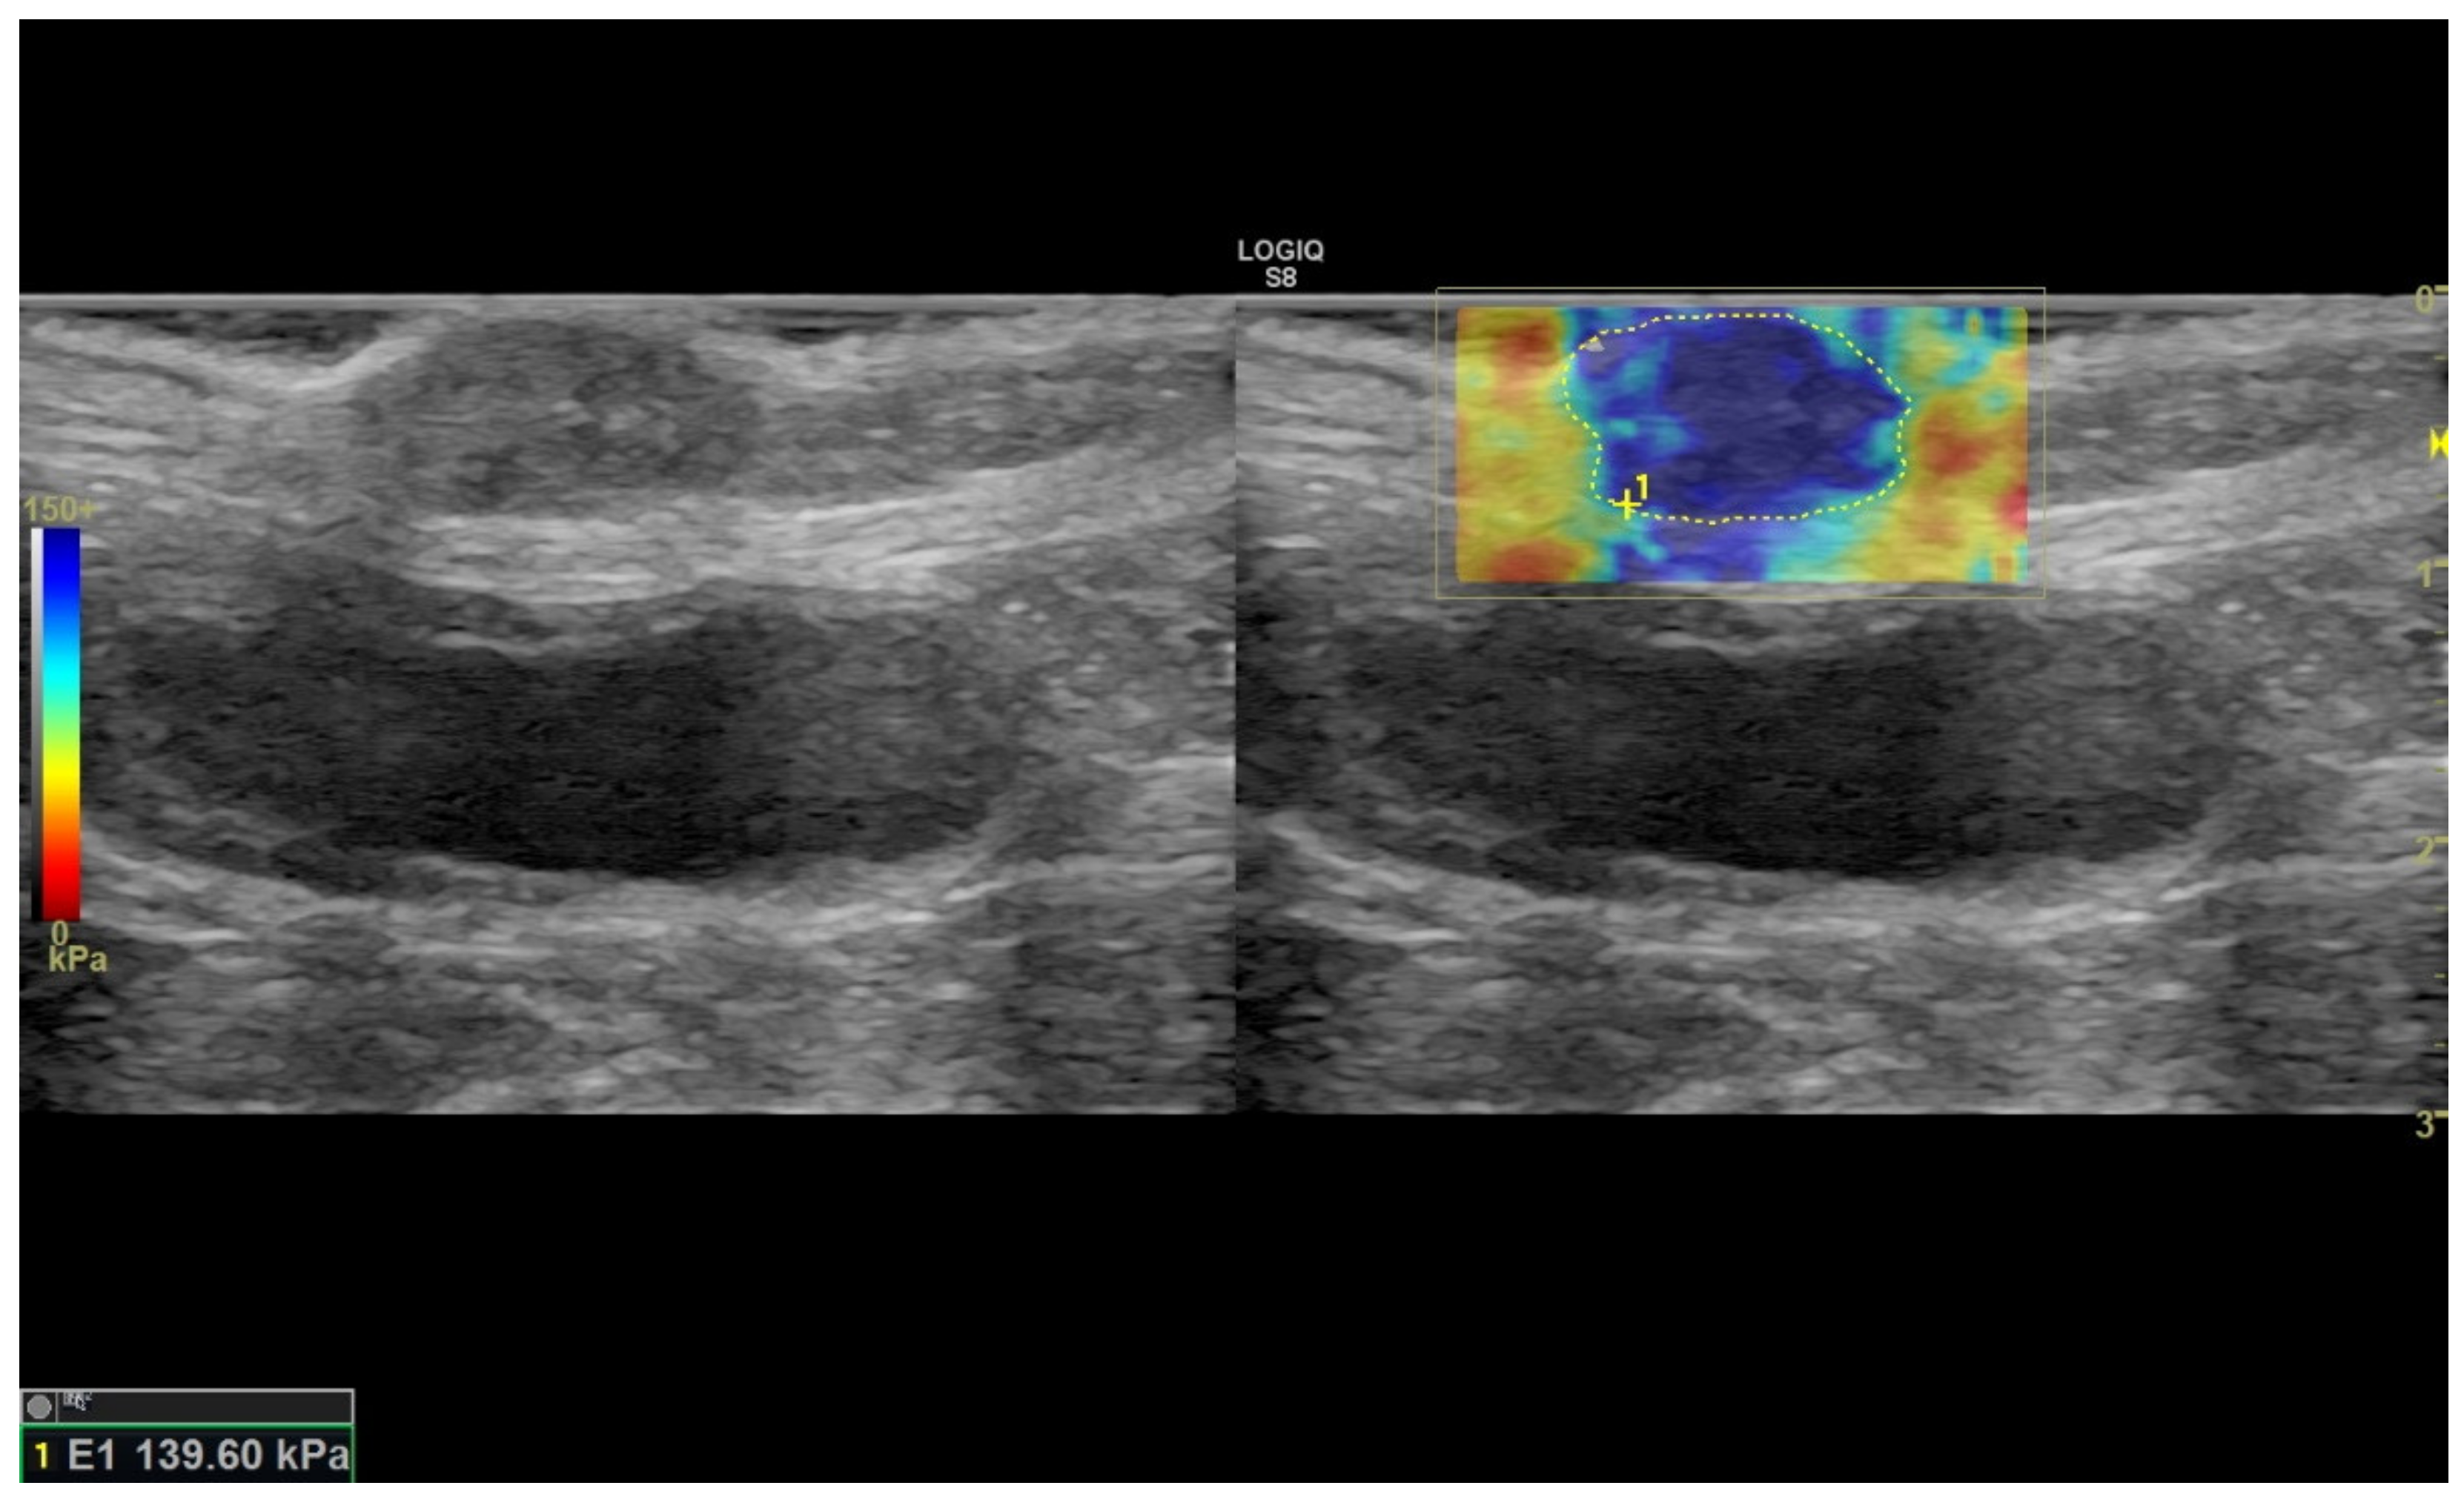

2.2. Ultrasound Sonoelastography

| SWE-S (kPA) | 100.8 ± 15.8 | 137.4 ± 4.8 | 115.4 ± 12.6 | 114.9 ± 4.9 | 120.1 ± 6.7 | 88.7 ± 56 | 115.5 ± 4.5 |